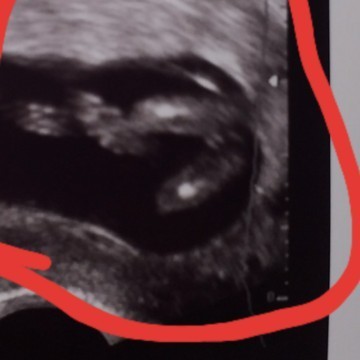

Mndurut bunda ini cewek kah ?? Usia 12 week

12 minggu belum bisa diliat JK nya bun stau saya